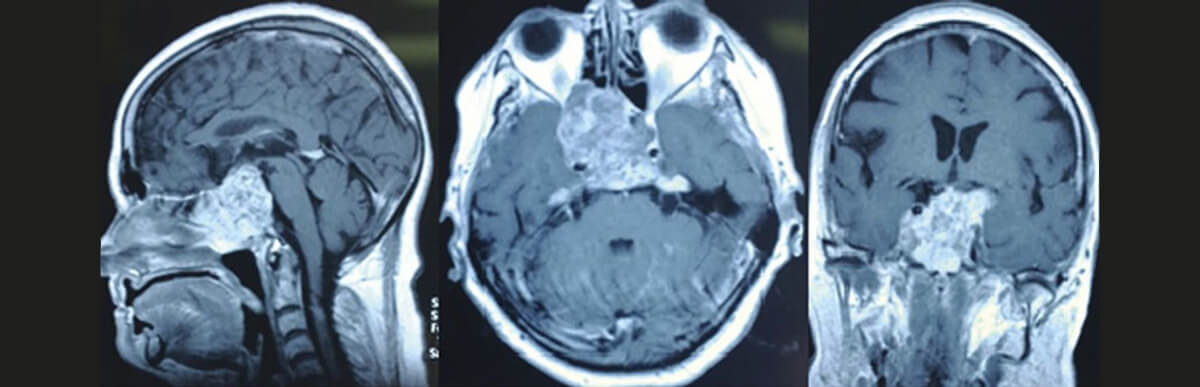

- Магнитно-резонансная томография (МРТ). Это основной метод визуализации, который позволяет с высокой точностью оценить мягкие ткани: саму опухоль, головной мозг, нервы. МРТ с контрастным усилением помогает определить границы образования и его взаимоотношение с окружающими структурами.

Все эти данные загружаются в специальную навигационную станцию. Это позволяет создать трехмерную модель головы пациента, на которой хирург может виртуально спланировать ход операции, выбрав самый безопасный путь к патологии. Такая технология, называемая нейронавигацией, работает как GPS-система во время самого вмешательства, повышая его точность.